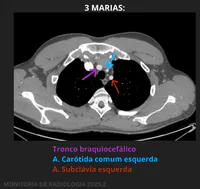

Como é chamado o conjunto de estruturas apontadas? Qual o nome de cada uma?

3 marias / SETA ROXA: Tronco braquiocefálico / SETA AZUL: A. Carótida comum esquerda / SETA VERMELHA: A. Subclávia esquerda

3 marias / SETA ROXA: Tronco braquiocefálico / SETA AZUL: A. Coronária direita / SETA VERMELHA: A. Subclávia direita

3 artérias. SETA ROXA: A. Subclávia esquerda / SETA AZUL: Tronco braquiocefálico / SETA VERMELHA: A. Carótida comum esquerda

3 marias. SETA ROXA: A. Subclávia esquerda / SETA AZUL: Tronco braquiocefálico / SETA VERMELHA: A. Carótida comum esquerda

“Teu Braço, Com um Cheiro Estranho, Seu Estranho”